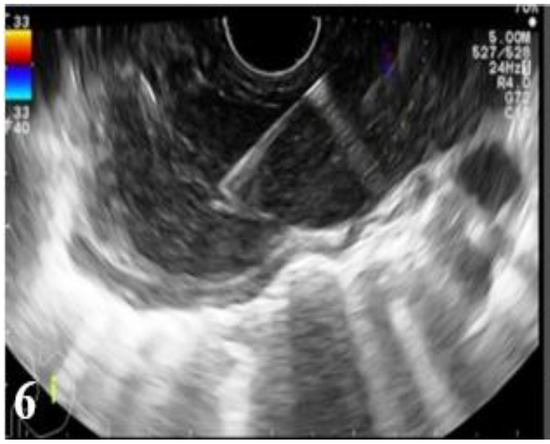

Figure 5.

EUS images: endoscopically guided fine needle aspiration (FNA) biopsy of a malignant mediastinal adenopathy from an esophageal carcinoma (part 1).